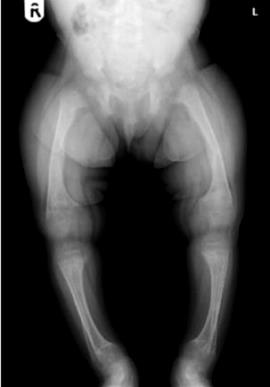

Típica deformación de piernas en el raquitismo

La más pequeña presenta raquitismo, enfermedad que afecta a niños desnutridos y no sólo les deforma los huesos y abulta su tórax, sino que su osamenta se vuelve frágil y vulnerable a las fracturas.